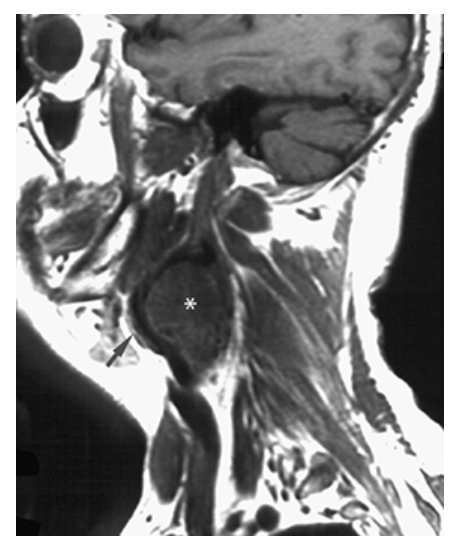

What does the figure show?

Glomus Tumor (Glomus Vagala). T1-weighted left parasagittal image shows an intermediate signal mass (asterisk) of the upper neck at the carotid bifurcation. The external carotid artery (arrow) is displaced anteriorly.